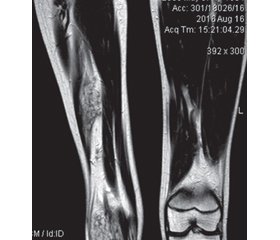

Для малих ВМ характерне ураження певного виду тканин, наприклад, при ізольованому ураженні двоголового м’яза стегна (рис. 3) ураження обмежене м’язовою тканиною, відмежована ВМ розташована в ділянці шиї в межах підшкірної клітковини (рис. 4).

Дифузне ураження великої площі м’язів кінцівок призводить до їх атрофії, що візуально проявляється зменшенням діаметра ураженої кінцівки порівняно зі здоровою, ускладненням гемартрозу є контрактура суглоба та вкорочення кінцівки (рис. 6).